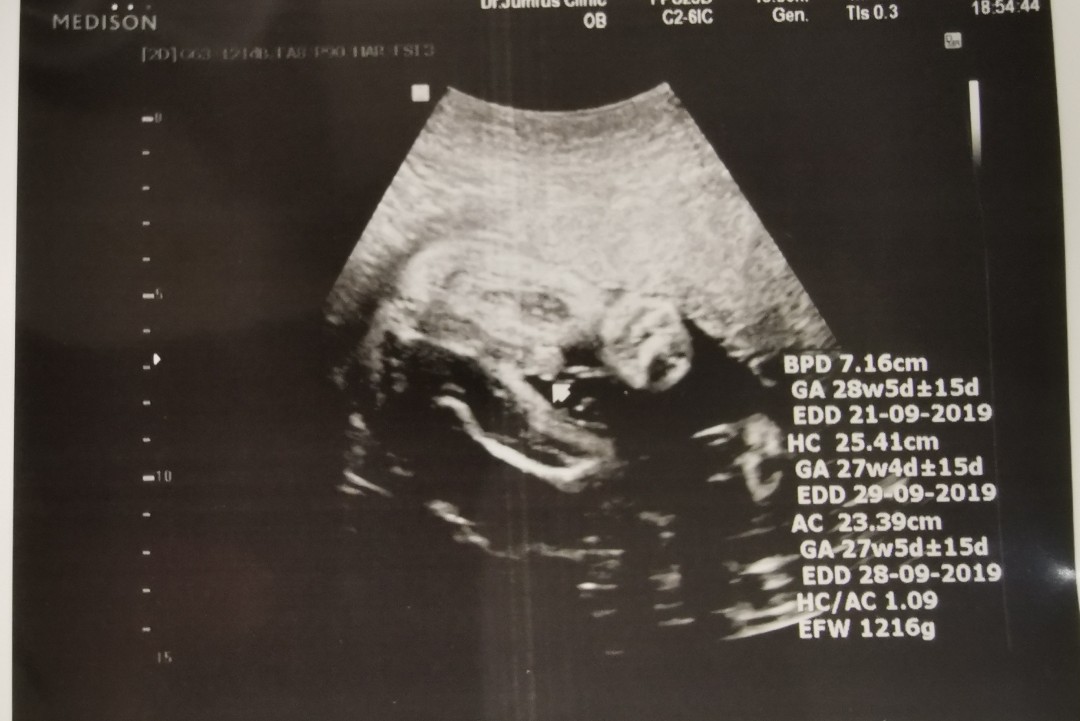

ชายจ้า 28 ธค